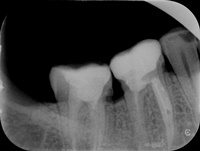

Trzykanałowa górna czwórka, nieczęsty przypadek.

Pacjentka zgłosiła się z bólem. Ząb prawa dolna czwórka po leczeniu kanałowym. Nawracające dolegliwości bólowe, od kilku lat okresowo zaostrzające się. Podjęto decyzję o rewizji leczenia kanałowego. Udróżniono kanał korzeniowy, oraz odnaleziono kanał dodatkowy. Zdjęcie początkowe i zdjęcie po leczeniu endodontycznym pod mikroskopem.